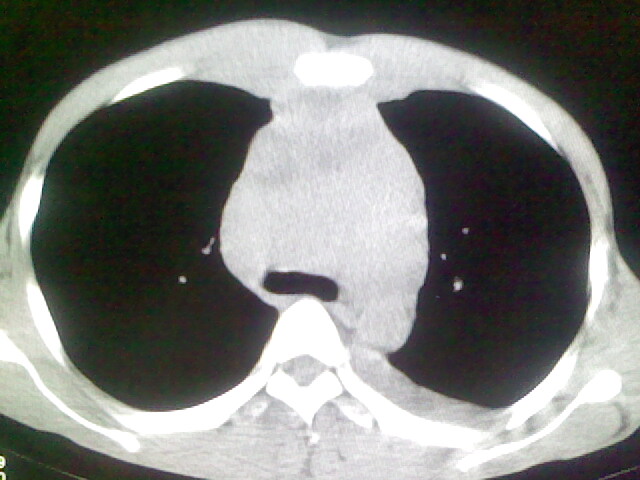

以下是引用杀毒软件在2008-9-3 6:11:00的发言:[br]侵袭性胸腺瘤------一般不侵到气管旁[br][br]考虑----纵隔淋巴瘤,心包及胸膜受累

以下是引用wzr在2008-9-3 5:30:00的发言:[br]侵袭性胸腺瘤

以下是引用随光逐影在2008-9-3 7:07:00的发言:[br]1)考虑淋巴瘤可能。2)双侧胸腔积液(以左侧为甚)。3)心包积液。